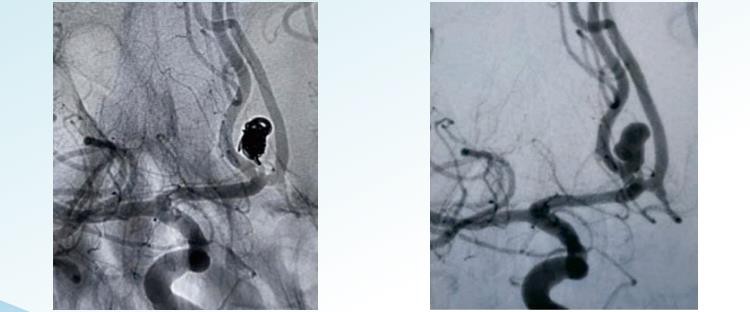

RenovaTModvojivi sustav namotavanja aneurizme nudi nasumične, spiralne i 3D odvojive opcije za endovaskularnu embolizaciju u promjerima od 1 do 22 m. Dizajniran je za embolizaciju aneurizme od okvira do kraja i uključuje zavojnice posebno oblikovane za postizanje koncentričnog punjenja aneurizme i zavojnice velikog volumena za postizanje velike gustoće pakiranja. Nasumično namotavanje je najjednostavniji i najstariji oblik tehnike namotavanja aneurizme. Uključuje umetanje jedne spirale ili skupine spirala u aneurizmu. Zavojnice su obično izrađene od platine i tanke su i čvrsto smotane kako bi se spriječilo stvaranje praznina ili prostora u vrećici. Spiralno namotavanje uključuje upotrebu duže, tanke žice koja je spiralno smotana oko sebe, tvoreći strukturu-nalik na oprugu. Žica se umetne u aneurizmu u ispravljenom obliku, a kada uđe unutra, dopušta joj se da se namota i proširi kako bi ispunila vrećicu aneurizme. Spiralne zavojnice su šire i tješnje postavljene od nasumičnih zavojnica, čime se omogućuje bolja okluzija aneurizme. 3D zavojnica uključuje upotrebu posebno-dizajnirane zavojnice, koja se izrađuje korištenjem kompjuteriziranog procesa snimanja koji stvara točan tro{14}}dimenzionalni model aneurizme. Zavojnica je proizvedena tako da točno odgovara veličini i obliku aneurizme. Ova vrsta zavojnice dizajnirana je tako da čvrsto pristaje u vrećicu aneurizme, pruža izvrsnu okluziju i smanjuje rizik od komplikacija. 3D zavojnice posebno su učinkovite u liječenju aneurizmi do kojih je teško doći ili u krhkim krvnim žilama.

5. Čvrsto uokvirite, ravnomjerno ispunite i završite traženjem šupljina unutar aneurizme.